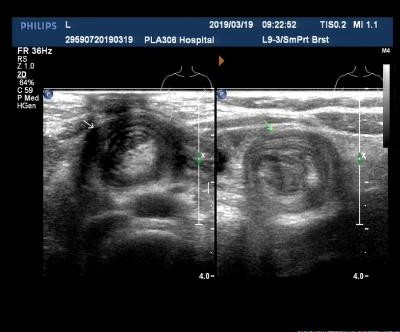

病理:套叠肠管横断面有三个筒,外筒为鞘部,中筒、内筒为套入部(图1、2)。外筒与中筒以黏膜面相接触,中筒和内筒以浆膜面接触,由于鞘部肠管持续痉挛,使套入部分肠管出现血运障碍,表现为淤血性坏死,同时鞘部肠管因强烈痉挛及扩张而发生缺血性坏死,易穿孔。

超声表现:腹部可探及包块,横断面呈多层"同心圆"征(图3),纵断面呈多层肠管平行排列的"套筒"征(图4),超声多普勒检查提示包块内血流信号呈点状散在分布(图5);或观察到动静脉频谱,提示肠管受压的症状轻,循环良好,包块内未显示血流信号或血流信号稀少,提示肠管可能存在缺血坏死的症状。部分患儿包块及周围肠系膜内可探及增大的淋巴结(图6)。

图3. 肠套叠横切同心圆征

图4. 肠套叠纵切套筒征